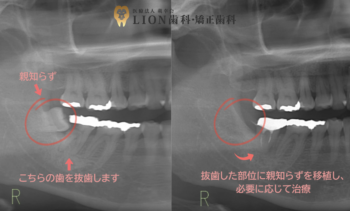

1.診査・診断

レントゲンやCTで親知らずと移植部位を精密に確認します。

2.抜歯・移植

親知らずを丁寧に抜歯し、失った歯の場所に植え替えます。